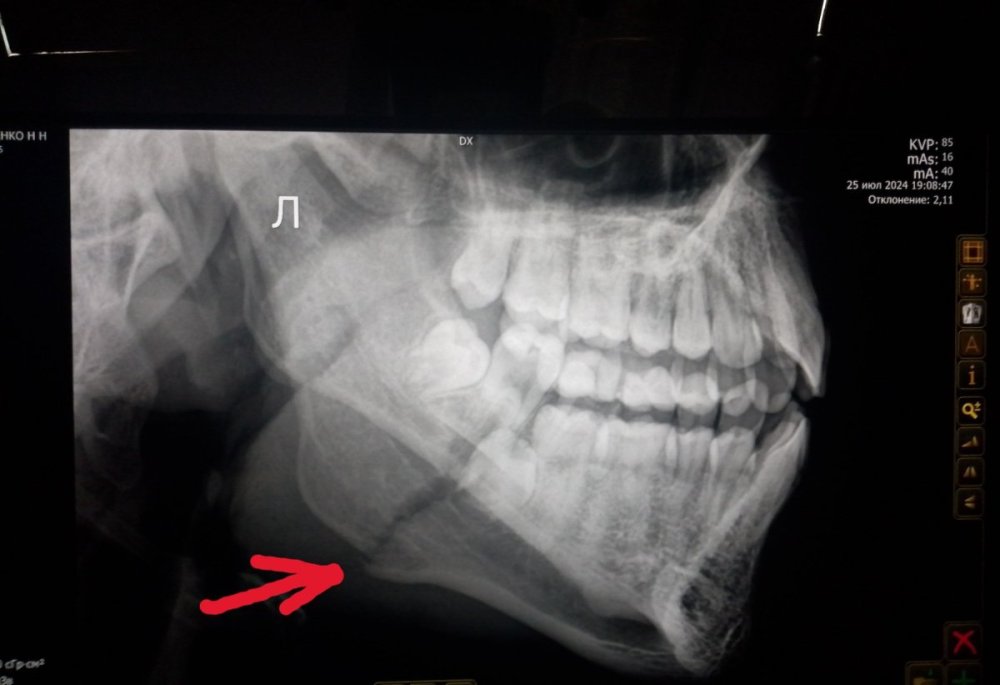

Скрытый текст

на   снимке  череп, челюстная   часть, боковая   проекция   и   перелом   нижней   челюсти ( указала  стрелочкой)

Кому  то    "вдарили"  в  челюсть..)